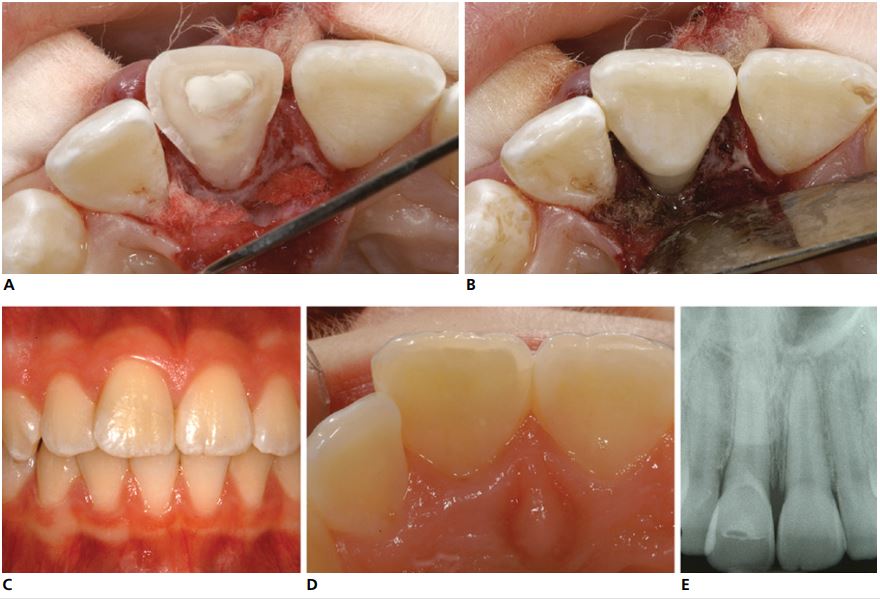

Thông thường nhất, đường gãy bắt đầu rìa cắn vài mm về phía mặt ngoài và đi theo đường chéo đến bên dưới khe nướu ở mặt trong. Các mảnh này thường chỉ bị di lệch một chút, mảnh thân răng được giữ ở nguyên vị trí nhờ các sợi của dây chằng nha chu và/hoặc tủy răng (Hình 14.3).

Sự di lệch của mảnh thân răng thường nhỏ nên đường gãy thường bị bỏ qua, đặc biệt là ở các vùng phía sau.